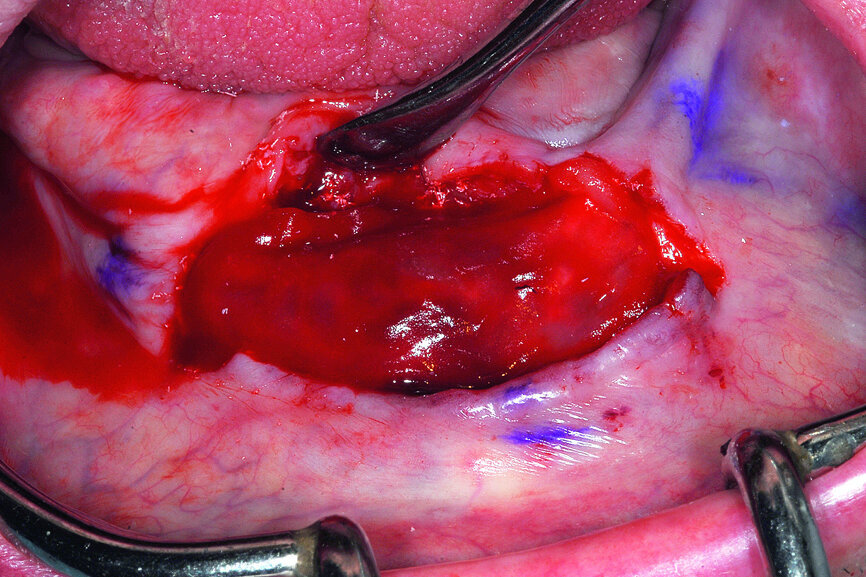

Once the offending element was removed, the plan was to reduce the knife-edged ridge to gain appropriate width for implant placement. The reduction was accomplished in a free-hand method based upon the position and location of the mental foramen on either side of the symphysis. Based upon a thorough review of the CBCT scan data the expected hollow area of bone in the anterior symphysis was exposed (Fig. 15).

Fig. 15: The anterior symphysis revealing the anterior ‘hollow’ symphysis.

The cross-sectional images revealed the presence of a thick facial buccal plate of bone in some areas, thinner in others, and a thick lingual plate of bone generally. The surprise was in the symphysis, a hollow area in the anterior central area exactly where implants would be placed! Other hollow areas and intraosseous vessels were noted (see arrows, Fig. 10). The ‘hollow’ areas in the anterior symphysis are as illustrated in the 3-D reconstructed volumes with four simulated implants in an occlusal view.